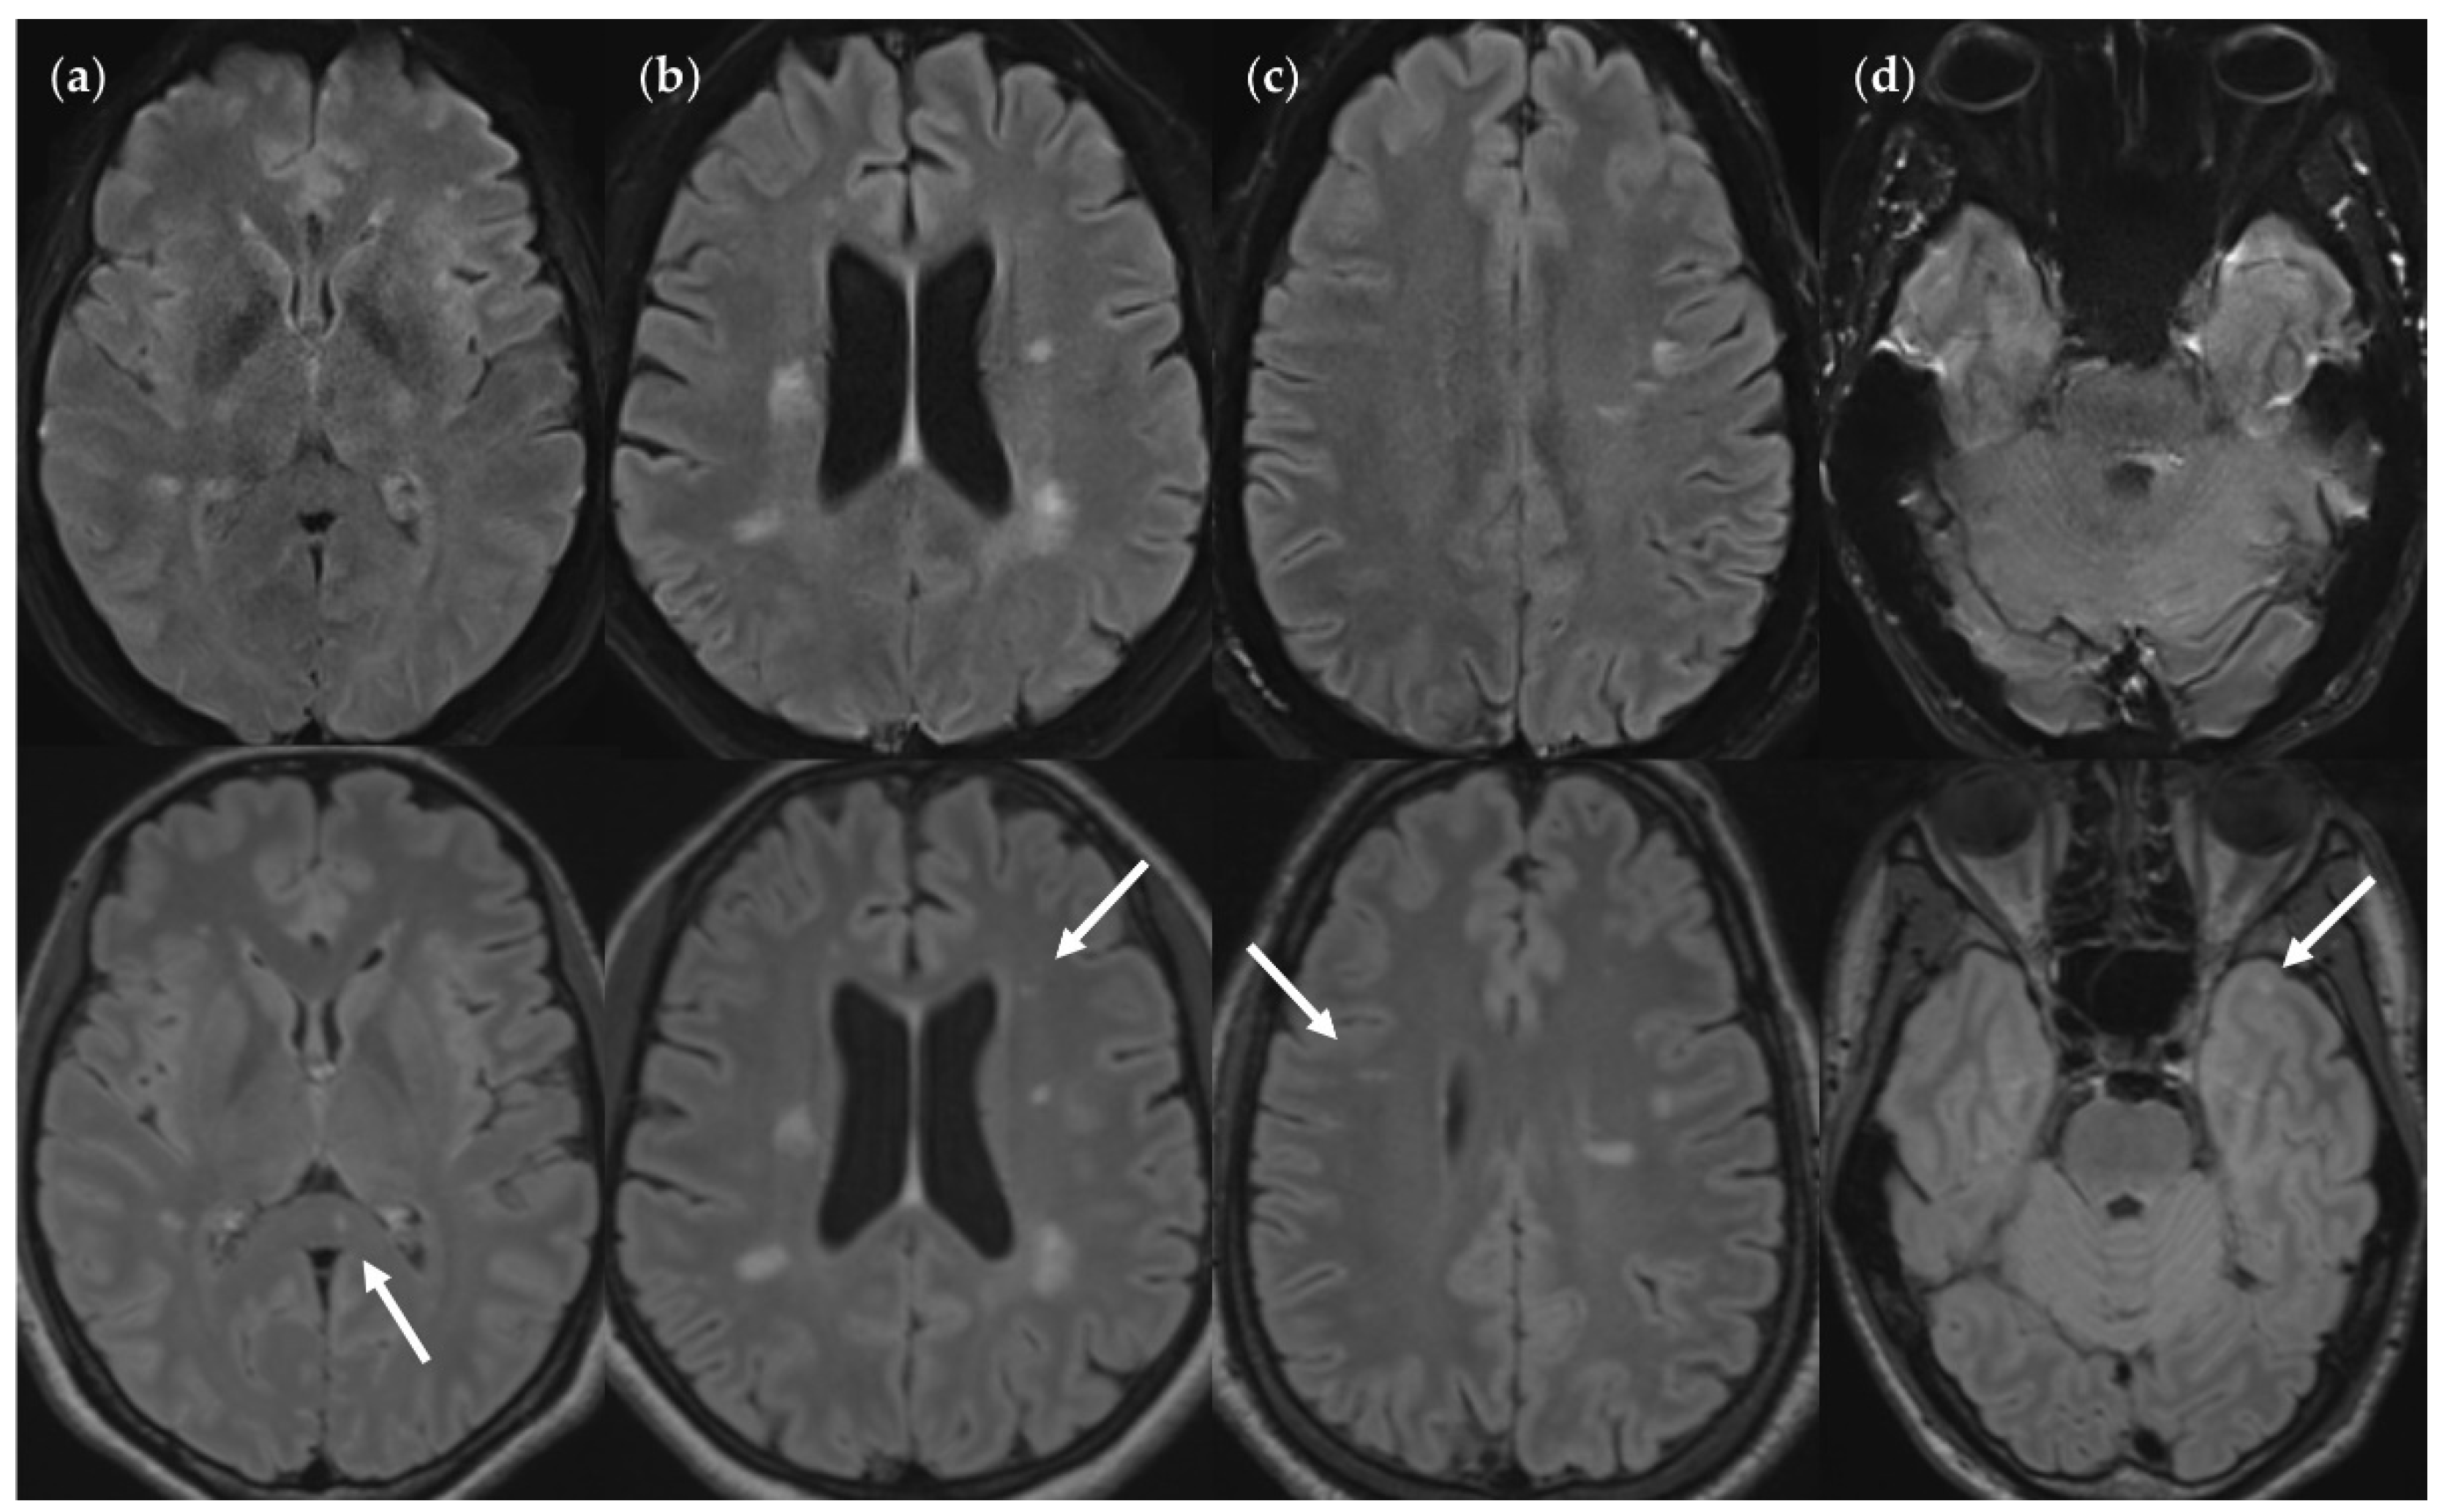

Figure 7.

FNUF lesions (top row) contrasted with their TP3Da counterparts (arrow, bottom row). The images also show several other lesions. (a) Lesion in the splenium of the corpus callosum (approx. 3 mm × 2 mm). Causes for it not being detected may be image noise and slice thickness/slice gaps. (b) Left frontal lesion (approx. 3 mm × 1 mm). Causes may be associated with slice thickness/contrast as well as image noise. (c) Thin right frontal lesion (approx. 7 mm × 1 mm). It was mistaken for cortex in the FLAIRUF image. (d) Left temporopolar lesion (approx. 3 mm × 2 mm). It was not recognized as such in the FLAIRUF image owing to commonly occurring distortions within this region.Note. Corresponding slices could not be positioned exactly identically for two reasons: Different slice thicknesses including slice gaps (c) and non-parallel slice inclinations (d).